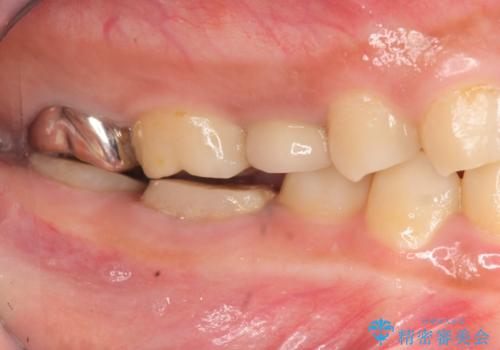

歯冠長延長術・骨隆起除去を行った、スペースの少ないセラミック治療

- 治療途中の奥歯の治療の続きを希望され、来院されました。

治療途中で長期間放置していたため、歯が歯ぐきから挺出(伸びてくる)してしまい、十分に強度を担保できるセラミッククラウンを装着するスペースが不足した状態です。

加えて、舌の邪魔になっている骨隆起や根尖病変といった問題を歯周外科・精密根管治療を行い、しっかりとスペースを確保したのちセラミッククラウンを作製していきます。